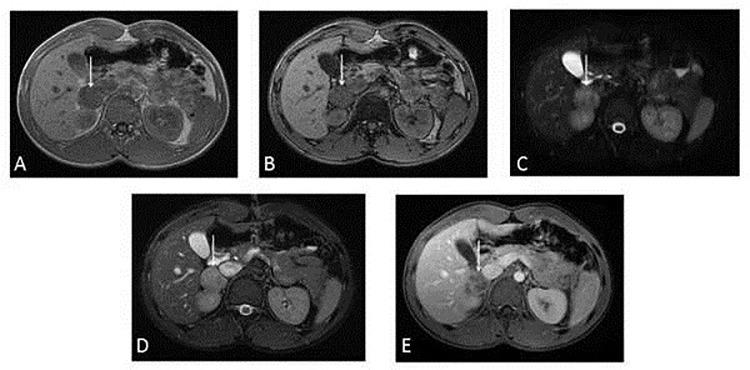

Peripheral neuroblastic tumors are extremely rare in the adult with less just over 20 cases involving adrenal gland described in the literature. We reported herewith the case of a 22-year-old young male who presented with epigastric pain and diarrhea. Imaging studies documented a 3.5cm x 3cm x 4cm solid well-circumscribed right adrenal mass, of heterogeneous structure and with fine calcifications. The lesion turned negative at MIBG scintigraphy. A right robotic-assisted adrenalectomy was performed leading to complete excision of the lesion without complications. Histology was consistent with intermixed stroma-rich ganglioneuroblastoma. A wait-and-see strategy was considered adequate. Two years after diagnosis patient is alive disease-free. Although the definitive diagnosis of a peripheral neuroblastic tumor is obtained after histopathological analysis, CT, and MRI are helpful to further characterize masses and useful in pretreatment risk stratification. Clinicians should be aware of the possibility of GNB development in adult population and its malignant potential.

外周神经母细胞瘤在成人中极为罕见,文献中报道的累及肾上腺的病例仅有20多例。我们在此报告一例22岁年轻男性,表现为上腹部疼痛和腹泻。影像学检查发现右肾上腺有一个3.5厘米×3厘米×4厘米的实性、边界清晰的肿块,结构不均质,有细小钙化。该病变在间碘苄胍(MIBG)闪烁扫描中呈阴性。实施了机器人辅助右肾上腺切除术,病变被完整切除,无并发症。组织学检查结果符合富含间质的混合型神经节神经母细胞瘤。采取观察等待策略被认为是合适的。诊断两年后,患者存活且无疾病。虽然外周神经母细胞瘤的明确诊断需经组织病理学分析得出,但CT和MRI有助于进一步明确肿块特征,且对治疗前风险分层有用。临床医生应意识到成人发生神经节神经母细胞瘤的可能性及其恶性潜能。